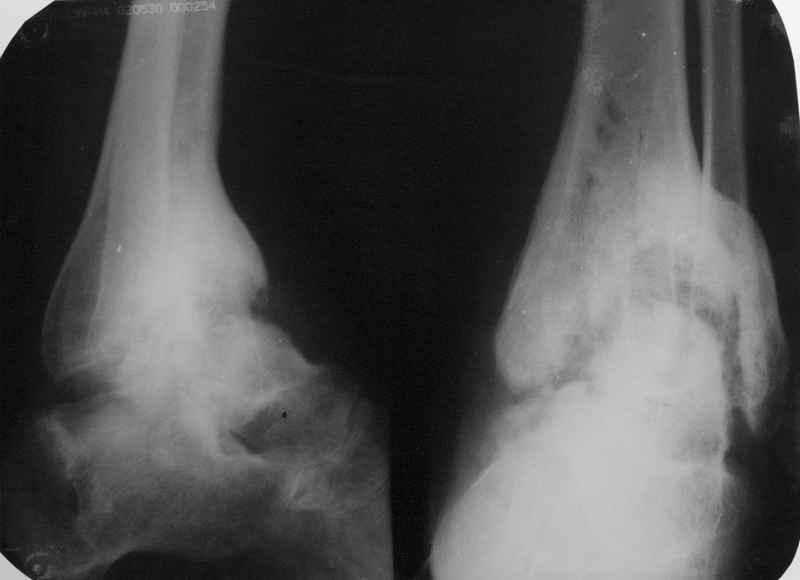

Пациентка Б. получила травму 2001 году в результате падения с высоты. За это время дважды выполнялись неудачные попытки артродезирования голеностопного сустава. Больная перед нами поставила одну задачу - восстановить опороспосонбность левой нижней конечности и только. Принято решение выполнить кейдж-артродезирование левого голеностопного сустава блокируемым интрамедуллярным гвоздем с установкой сетчатого опорного трансплантата, костной аутопластикой плюс Chronos. С целью профилактики рецидива деформации выполнили ахиллотомию (считаем, что неудачи предшествующих операций связаны с варусной тягой ахиллова сухожилия в ррезцльтате неправильно сросшегося перелома пяточной кости). На сегодняшний день - два месяца с момента операции. Пациентка перемещается в циркулярной повязке с полной нагрузкой на больную ногу.

В данном случае мы столкнулись с проблемой мощного гиперпластического процесса в области голеностопного сустава, невозможностью или высокой

травматичность сближения артродезируемых оверхностей, поэтому решили применить кейдж из никилида титана и костную комбинированную пластику, к области применения добавили артродезирование. На нашем форуме уже показывали

Кейдж в голеностоп - свежая мысль - отлично! Но беда в том, что стопа как находилась в переднем подвывихе - так в нем и осталась. Боюсь, что даже при формировании костного анкилоза, пациентка вряд-ли будет довольна опороспосбностью ноги ввиду грубых биомеханических нарушений. На мой взляд, с учетом неправильно сросшегося перелома пяточной кости, следовало бы выполнить артродез голеностопного (с безжалостной резекцией заднего отдела большеберцовой кости), подтаранного и пяточнокубовидного суставов и, тем самым, коррекцию порочного положения стопы. Фиксация блокируемым стержнем - замечательно! И еще - в данной ситуации ахиллотомия сродни лечению коксартроза мазью хондроксид.

Пациентку беспокоила одна проблема - нестабильность, из-за которой ей приходилось опираться на наружный край стопы. Не было болей, она не страдала от укорочения конечности в той мере, чтобы решиться на операцию по восстановлению длины. Поэтому перед нами стояла одна задача: стабилизировать сегмент, выбрав наиболее комфортную для пациентки тактику. В прошлом больная перенесла две неудачные операции по артродезированию с общим сроком гипсовой иммобилизации около 1,5 лет. Аппарат мы посчитали менее приемлемым способом лечения в данной ситуации.